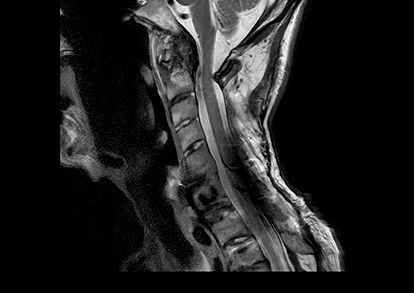

Addressing the issue of motion and low SNR in cervical spine imaging

Fairfax MRI Center evaluates the improvements brought by AIR™ Recon DL’s motion insensitive imaging when performing a spinal cord exam.